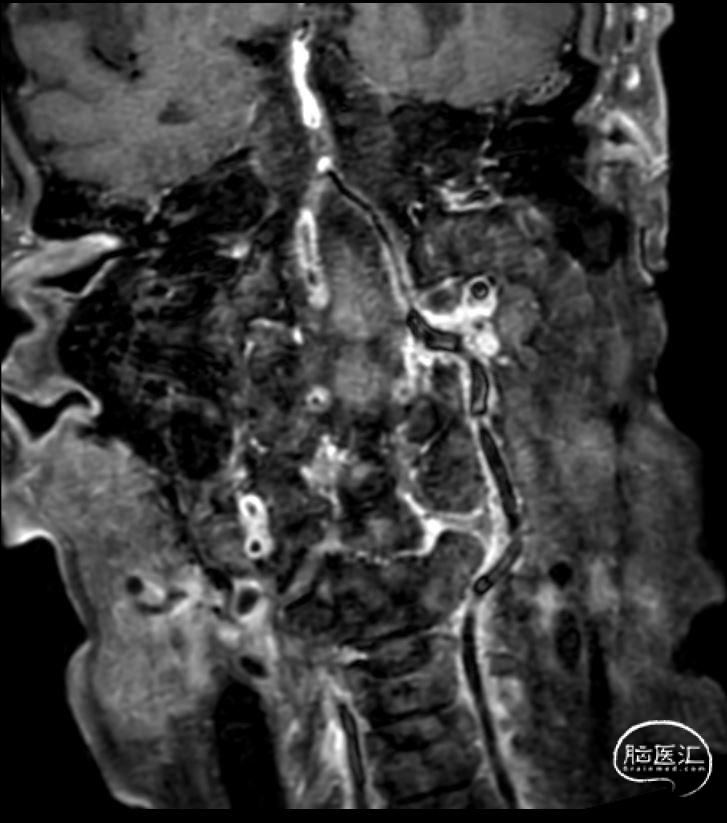

头颈部CTA:头颈部动脉粥样硬化,右侧椎动脉颅内段及两侧大脑后动脉重度狭窄,基底动脉闭塞。

➢2023年11月14日

头颅MRI平扫+HRMRI:脑桥、中脑急性/亚急性脑梗死;双侧桥臂变性。

HRMRI:基底动脉闭塞并斑块合并局部出血;左侧大脑后动脉P1段斑块形成,相应管腔闭塞,左侧椎动脉V2-V4段斑块形成,相应管腔中重度狭窄,左侧椎动脉V4段管壁弥漫性增厚,相应管腔中度狭窄;右侧大脑后动脉纤细。

主动脉弓造影:II型弓,牛角弓,双侧椎动脉纤细,动脉晚期显示基底动脉闭塞。

双侧颈内动脉造影,双侧大脑前动脉、双侧大脑中动脉未见明显异常,双侧后交通动脉纤细。

双侧椎动脉造影,右侧椎动脉V3段中度狭窄,基底动脉闭塞。